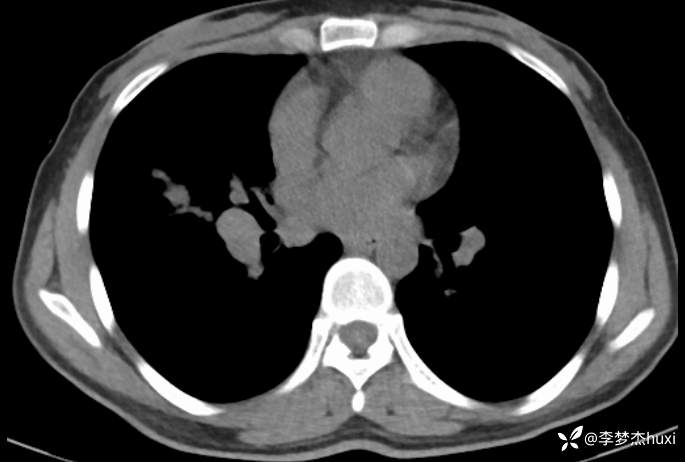

女性35岁,主因咳嗽、咳痰1月,胸部CT报肺炎,猜对乃神医!

女, 35 岁,主因咳嗽、咳痰1月于2025-11-05 08:46入院。

1.现病史:患者中年 女,患者于入院前1月“感冒”后出现咳嗽、咳痰,为黄白痰,不易咳出,无痰中带血,咽部刺痒不适,咳嗽明显,无胸痛,无胸闷、憋气,无恶心,未呕吐,无腹痛、腹泻,无尿频、尿急、尿痛,于院外口服药物(具体不详)治疗,病情未见好转,2025-11-4于我院门诊查胸部CT提示右肺炎症。为进一步诊治来我院;门诊以“肺炎”收入院 。

肺炎。